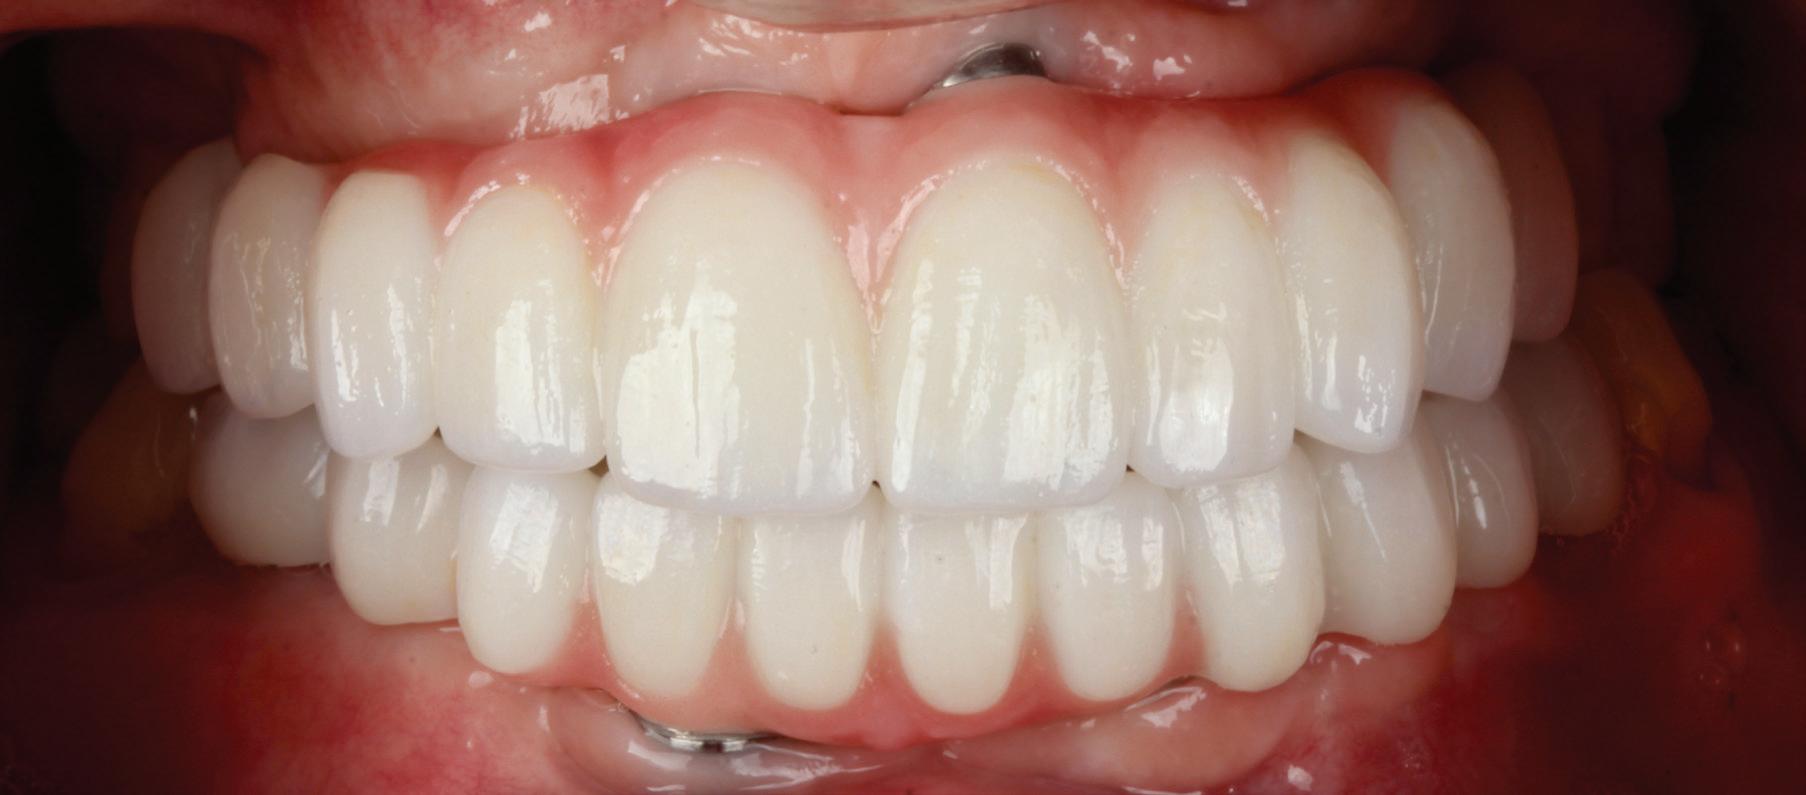

• Pacient cu restaurări deficitare pe dinți compromiși structural, tratamente endodontice eșuate, mobilitate avansată, pungi parodontale profunde, incisiv lateral absent congenital restaurat prin substituție canină inestetică, linie înaltă a zâmbetului. Rezolvarea? Colaborarea cu endodont, parodontolog, ortodont, protetician. Rezultatul? Succes clinic și satisfacția pacientului.

• Chirurgia implantară cu cea mai inteligentă planificare și mai precisă execuție va necesita în continuare un finisaj protetic care funcționează biomecanic și realizează o estetică naturală ideală individuală. Dacă există un aspect al tratamentului protetic cu provocări în era digitală, acesta ar consta în munca artistică minuțioasă a ceramistului, cu modelarea și pictarea dinților pentru a imita natura.

Colaborarea profesională și planificarea ghidată protetic sunt esențiale pentru rezultate predictibile de succes.